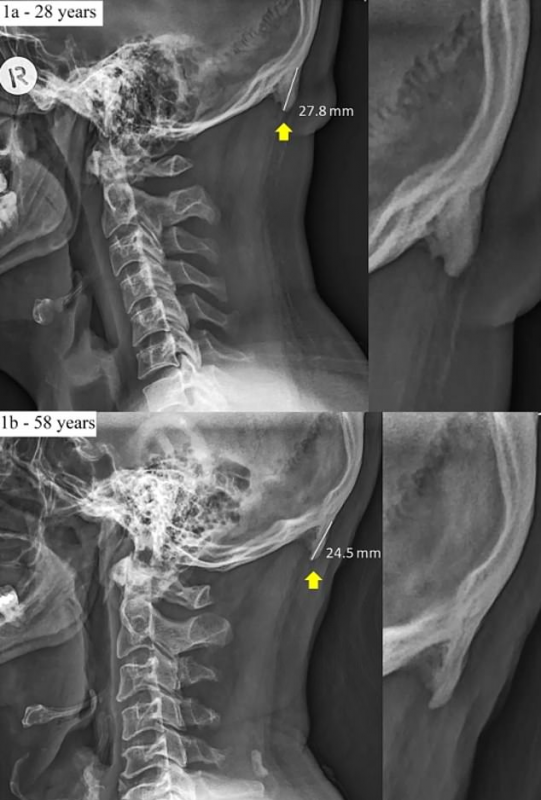

Проанализировав 1 200 рентгеновских снимков взрослых австралийцев, исследователи пришли к выводу, что у 41 процента из них в возрасте от 18 до 30 лет наблюдались такие отростки. У представителей других возрастных категорий они тоже наблюдались, однако на восемь процентов реже. В некоторых случаях наросты достигали в длину всего лишь одного сантиметра и были едва заметны, в то время как некоторые отростки были трехсантиметровыми.

Дэвид Шахар из Университета в Квинсленде рассказывает, что за второе десятилетие XXI века он сталкивался с подобными случаями все чаще. Он отметил, что подобные "дополнительные" кости называются энтезофитами и появляются, когда тело долго находится в напряжении и необычной позе.

Как предполагают эксперты, причиной появления костного отростка можно считать активное распространение смартфонов. Разговаривая посредством этих гаджетов, люди часто незаметно для себя немного наклоняют голову и вытягивают ее вперед, что и может послужить причиной появления энтезофитов.